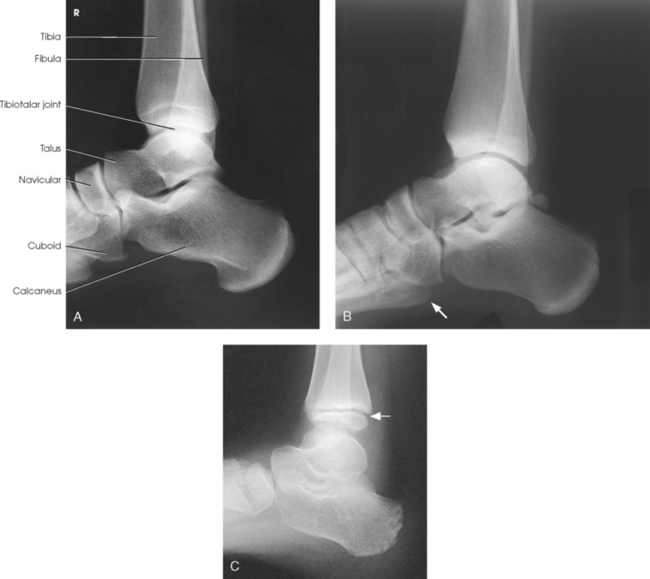

The distal end of the tibia (Fig. 6-5) is broad, and its medial surface is prolonged into a large process called the medial malleolus. Its anterolateral surface contains the anterior tubercle, which overlays the fibula. The lateral surface is flattened and contains the triangular fibular notch for articulation with the fibula. The surface under the distal tibia is smooth and shaped for articulation with the talus.

The fibula is slender compared with its length and consists of one body and two articular extremities. The proximal end of the fibula is expanded into a head, which articulates with the lateral condyle of the tibia. At the lateroposterior aspect of the head is a conic projection called the apex. The enlarged distal end of the fibula is the lateral malleolus. The lateral malleolus is pyramidal and marked by several depressions at its inferior and posterior surfaces. Viewed axially, the lateral malleolus lies approximately 15 to 20 degrees more posterior than the medial malleolus (see Fig. 6-5, C).

The ankle joint is commonly called the ankle mortise, or mortise joint. It is formed by the articulations between the lateral malleolus of the fibula and the inferior surface and medial malleolus of the tibia (Fig. 6-13, A). The mortise joint is often divided specifically into the talofibular and tibiofibular joints. These form a socket type of structure that articulates with the superior portion of the talus. The talus fits inside the mortise. The articulation is a synovial hinge type of joint. The primary action of the ankle joint is dorsiflexion (flexion) and plantar flexion (extension); however, in full plantar flexion, a small amount of rotation and abduction-adduction is permitted. The mortise joint also allows inversion and eversion of the foot. Other movements at the ankle largely depend on the gliding movements of the intertarsal joints, particularly the one between the talus and calcaneus.

The fibula articulates with the tibia at its distal and proximal ends. The distal tibiofibular joint is a fibrous syndesmosis joint allowing slight movement. The head of the fibula articulates with the posteroinferior surface of the lateral condyle of the tibia, which forms the proximal tibiofibular joint, which is a synovial gliding joint (see Fig. 6-13, A).